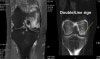

CT : 대퇴과 골괴사(Osteonecrosis of the femoral condyle)

MRI : 대퇴과 골괴사(Osteonecrosis of the femoral condyle)